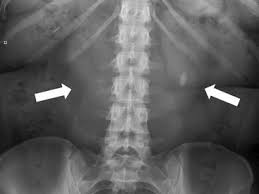

Kidney X Ray Images. The right kidney measures 10 7 cm and the left kidney measures 12 cm normal. This damage can be prevented by a feedback mechanism that determines the place of kidney stones depending on the images taken from eswl device.

Here are selected photos on this topic but full relevance is not guaranteed if you find that some photos violates copyright or have unacceptable properties please inform us about it. This damage can be prevented by a feedback mechanism that determines the place of kidney stones depending on the images taken from eswl device. Find x ray kidney stones stock images in hd and millions of other royalty free stock photos illustrations and vectors in the shutterstock collection.

Kidney x ray buy this stock illustration and explore similar illustrations at adobe stock. 0 public playlist includes this case. Until recently i ve only needed the nhs for short sharp interventions a tonsillectomy an appendectomy x rays and stitches. X rays are made by using external radiation to produce images of the body its organs and other internal structures for diagnostic purposes.